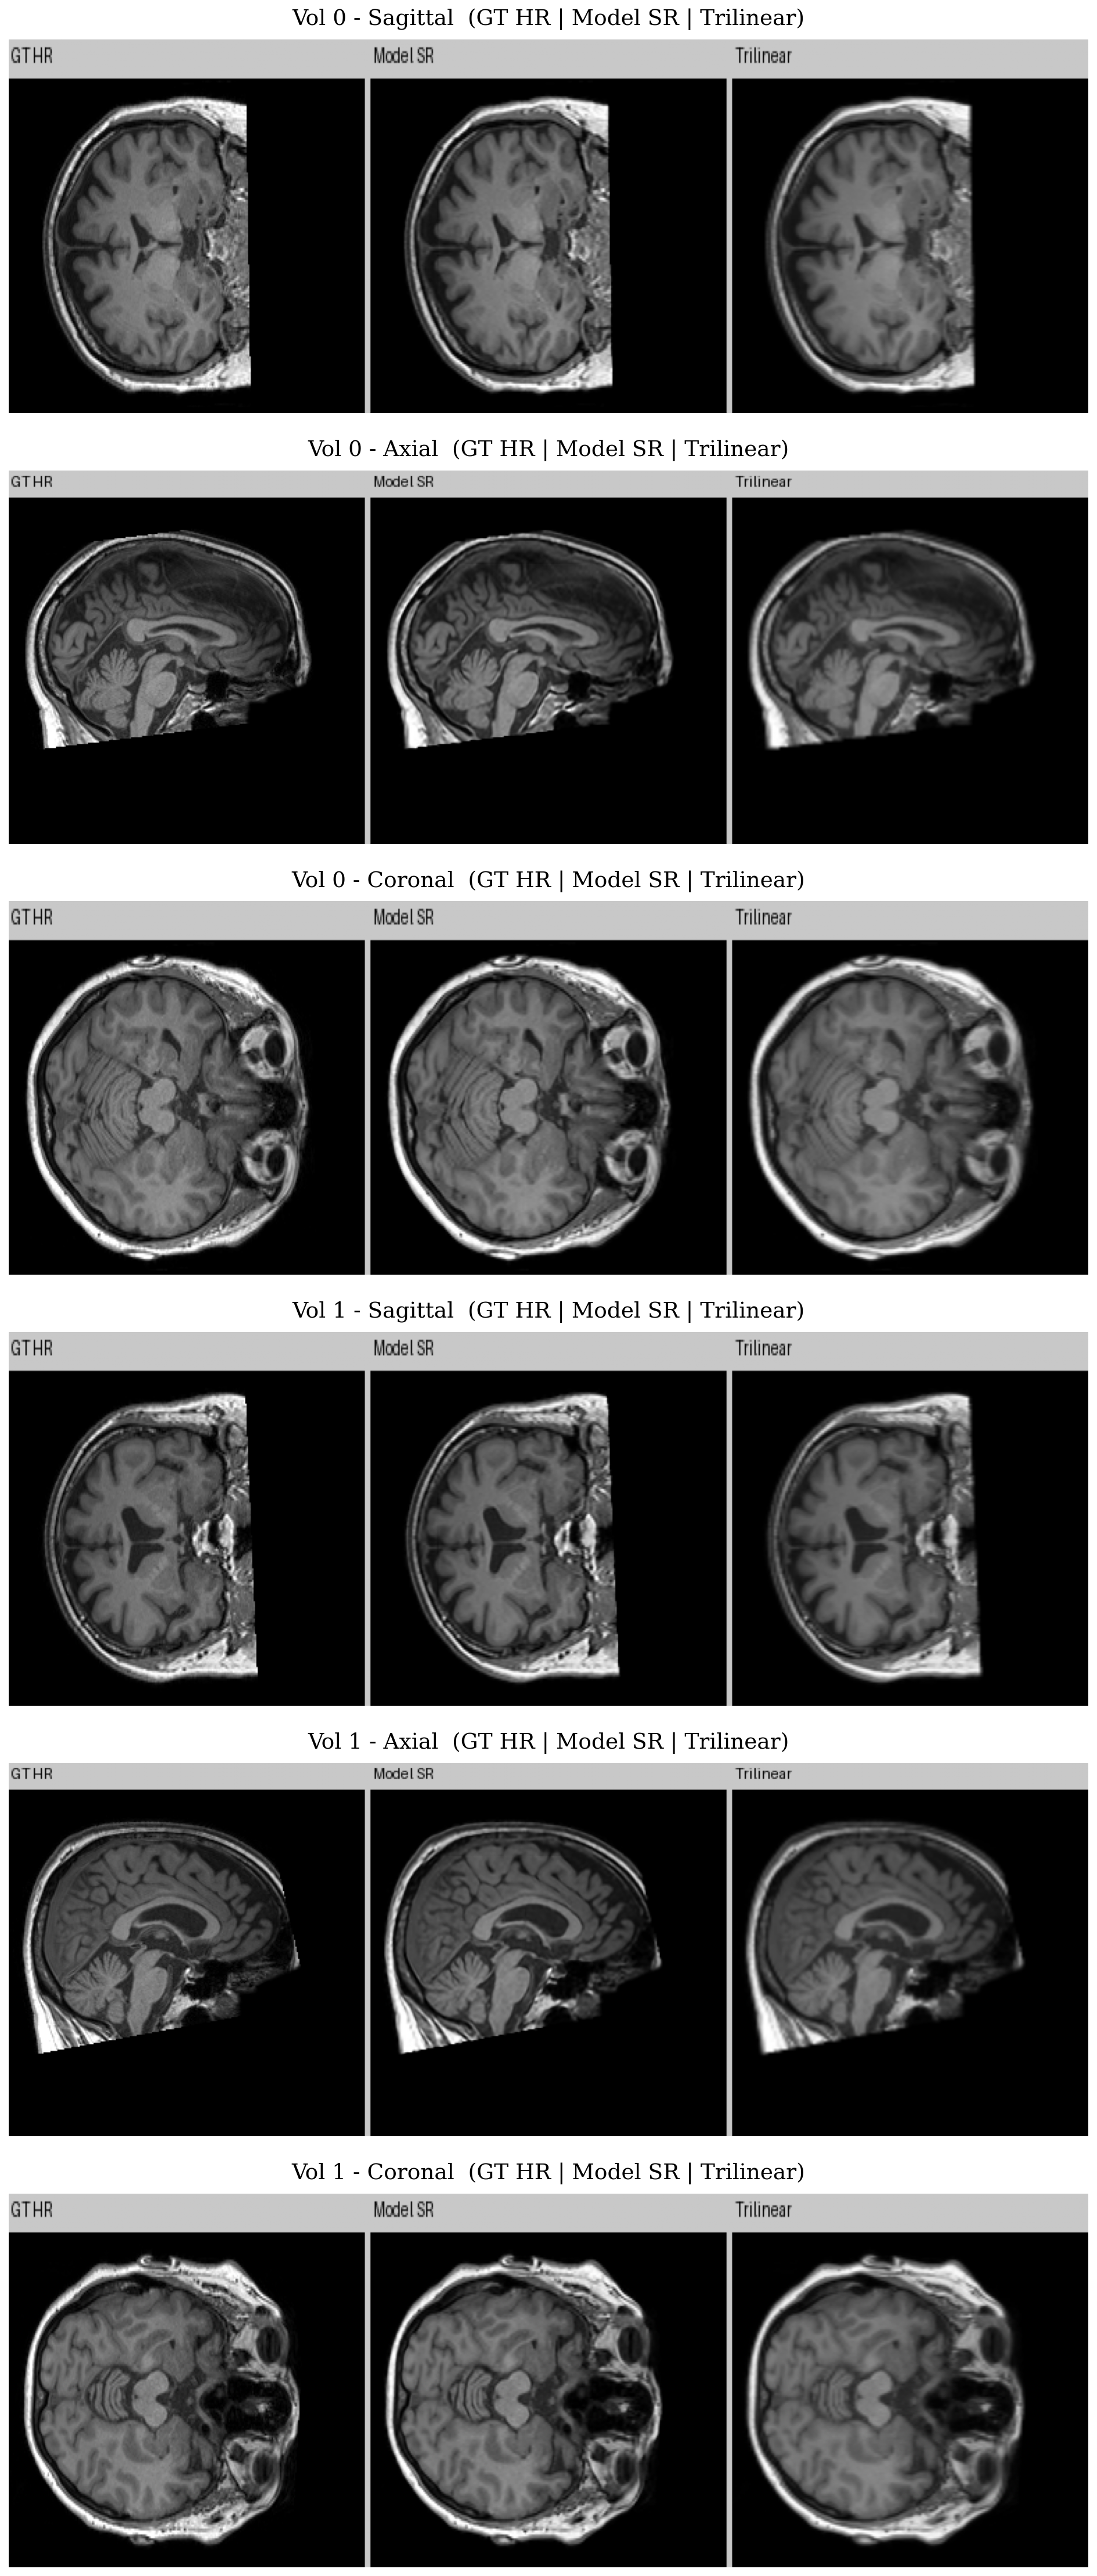

Visual Comparison (3D Model)

Ground truth HR, model prediction, and trilinear baseline across sagittal, axial, and coronal views: